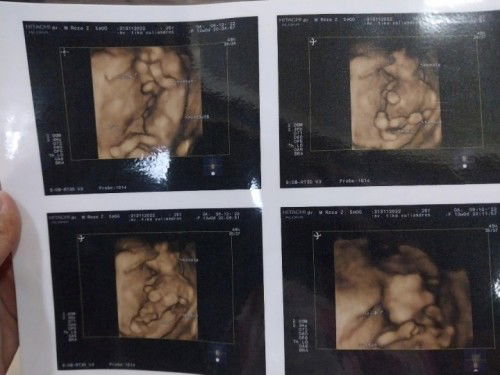

Hai bunda, disini ada yg hpl 24 juni?? Semalem habis usg 4d dan seperti ini janinnya 🥰🥰😘😘 semoga bunda dan bayinya sehat semua smpai nnti lahiran ya😇😇🙏🙏, apa yg dirasakan bunda skrang?? Kalau aku masih mual muntah, kadang2 sih.. tapi sering pusing, gak suka kayu putih juga